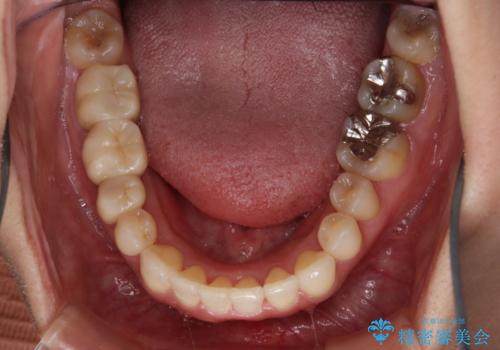

- 前歯のがたつきと反対咬合を主訴に来院されました。

インビザライン・クリンチェック(歯のシミュレーション)を行い、

インビザラインライトで治せる範囲であることを確認し治療を開始することになりました。

今回はクリンチェックを作成したのちに、枚数が少なくても可能であることが判明したためインビザラインライトでの治療を行いました。

最初はインビザラインモデレートパッケージの予定で契約をされていたので、金額も10万円以上安くなり仕上がりも満足頂きました。